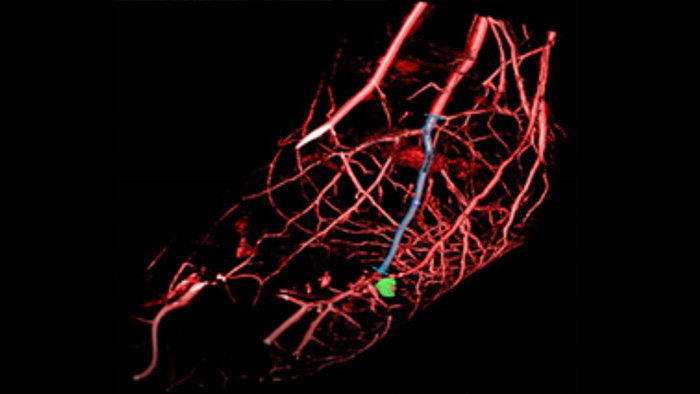

XperGuide offers live 3D image needle guidance, letting you bring percutaneous needle procedures into the Hybrid OR. It overlays live fluoroscopy and 3D soft tissue imaging data from previously acquired CT or MR scans or Philips XperCT, providing information on the needle path and target.

SmartCT Roadmap facilitates complex interventions by providing live 3D image guidance that can be segmented to emphasise target vessel and lesions, aiding navigation through complex vessel structures. All controlled via the touch screen at the table.